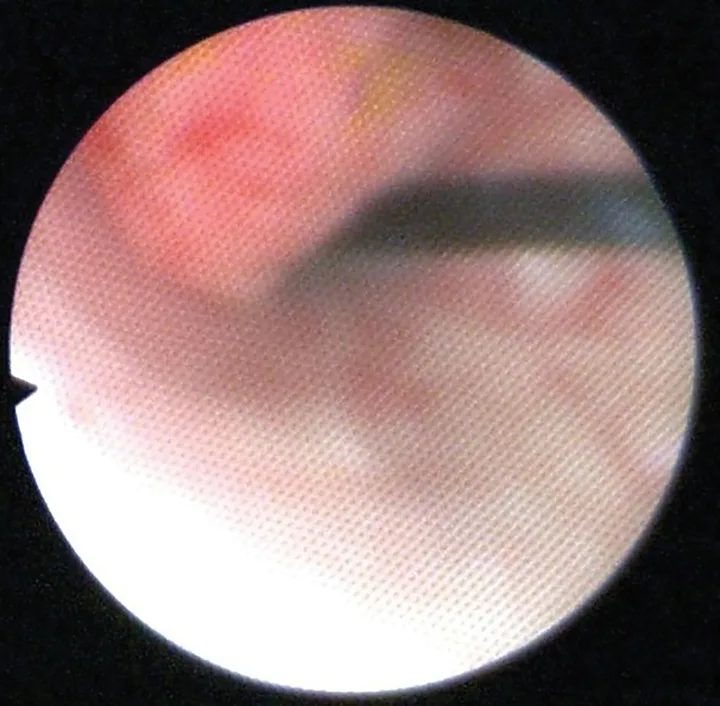

Abdominal ultrasound showed a mildly thickened cranioventral urinary bladder wall with a 6-mm irregular, polypoid, inhomogeneous mass extending into the lumen (Figure 1). No other abnormalities were identified in the abdomen. Cystoscopy revealed an irregular mass on the cranioventral wall with an area of ulceration and a fibrous tag protruding into the lumen (Figure 2). The remainder of the bladder appeared friable. Aerobic and Mycoplasma spp cultures of the bladder wall were negative. Histopathologic examination of biopsies showed mild lymphocytic cystitis.

FIGURE 2

Cystoscopic image of an ulcerated polypoid mass extending into the bladder lumen